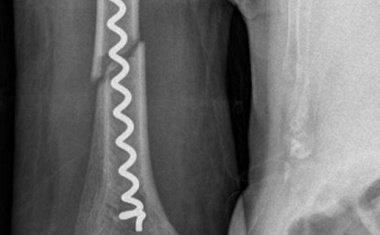

Gemeinsam mit Kooperationspartnern aus Wissenschaft und Industrie entwickelten Unfallchirurgen des Universitätsklinikums Jena eine neue minimalinvasive Versorgung von Frakturen des hinteren Beckenrings.